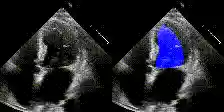

Examples

We show examples of our semantic segmentation for nine distinct patients below. Three patients have normal cardiac function, three have low ejection fractions, and three have arrhythmia. No human tracings for these patients were used by EchoNet-Dynamic.

| Normal | Low Ejection Fraction | Arrhythmia |